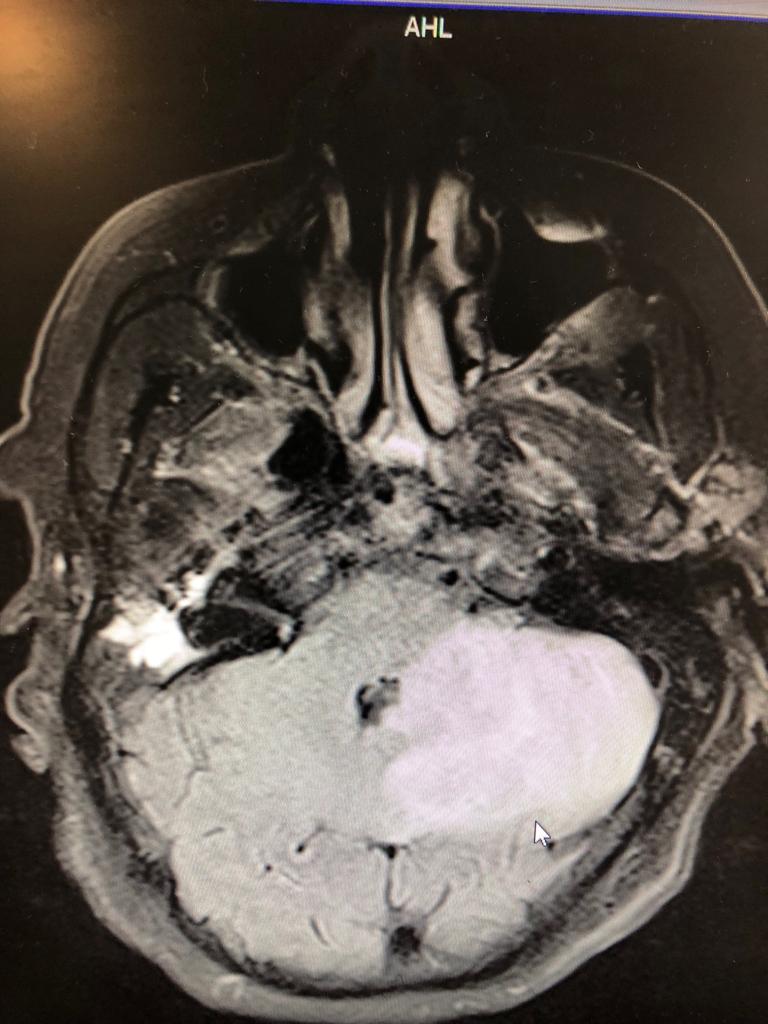

Ejemplo de Imagen Aqui Ejemplo de Imagen Aqui Ejemplo de Imagen Aqui Ejemplo de Imagen Aqui